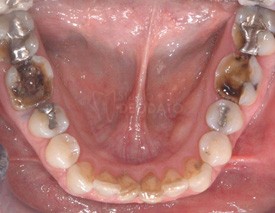

Caso Clinico risolto per mezzo di:

• 1 restauro diretto (otturazioni in composito) sul 34

• 9 restauri indiretti parziali (Intarsi in composito) sui 16, 15, 14, 24, 25, 36, 37, 45, 47.

• 2 restauri indiretti totali (Corone in ceramica) sui 26, 46.